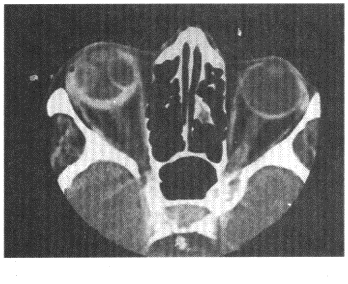

10.男,右眼外伤后视物不清,CT扫描如图所示,正确的描述或诊断是![]() |

| 正确答案:ABCD 解题思路:图示右侧眼环增厚,密度增高,眼球外侧密度增高影及内侧类圆形低密度影,视网膜区可见稍低密度影,综合患者病史考虑为右侧玻璃体出血及视网膜剥离,故ABCD正确。 |